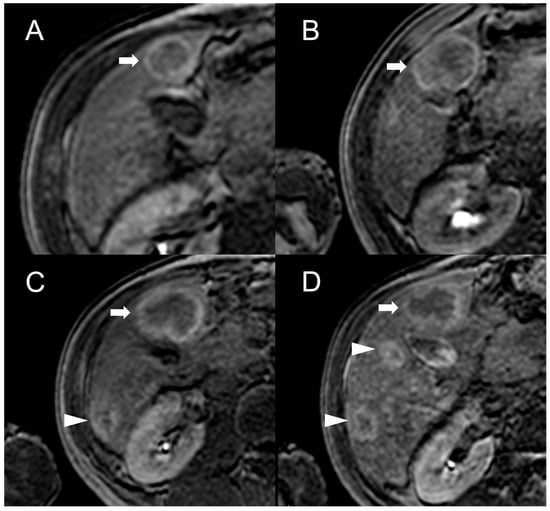

Figure 4.

MRI examinations of a 31-year-old male patient with Budd-Chiari syndrome performed in 2016 (A), 2017 (B), 2018 (C), and 2020 (D). Gradient-echo T1-weighted sequences (flip angle = 30°) acquired in the hepatobiliary phase revealed a 25 mm FNH-like RN (arrows) with central scar and peripheral hyperintensity in 2016 (A). The lesion size grew to 41 mm after 1 year (B) and further to 44 mm after 2 years (C), but it reduced to 35 mm in 2020 (D). Additionally, new FNH-like RNs appeared over time (arrowheads in C,D).